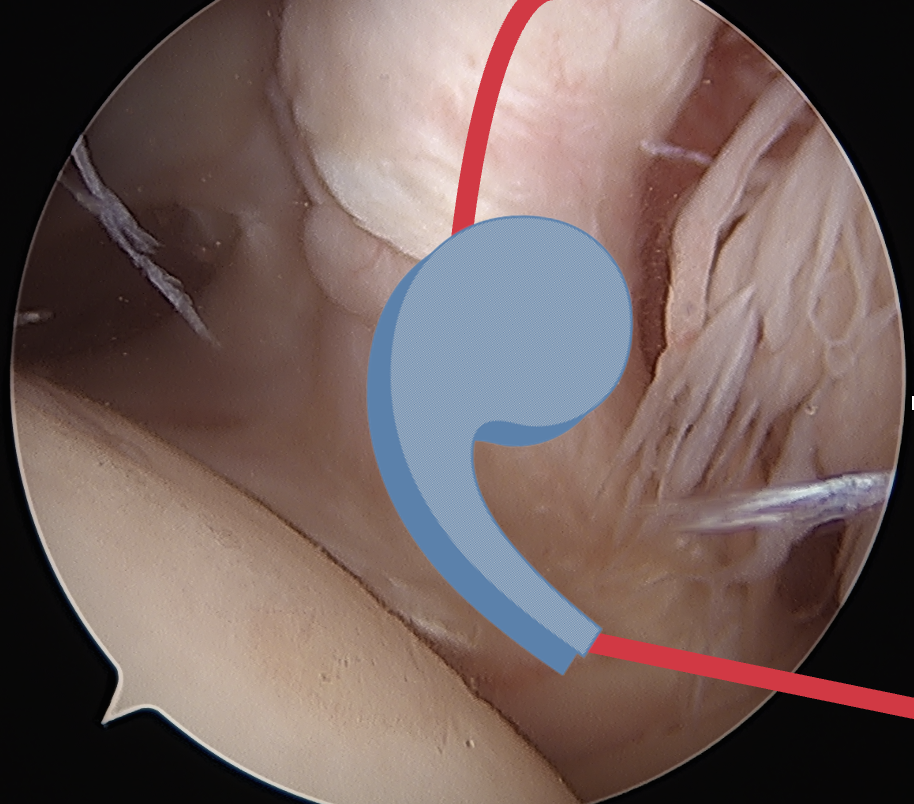

Comma sign

- medially retracted subscapularis tear

- exposes the superior insertion of superior glenohumeral ligament / coracohumeral ligament

Full thickness retracted subscapularis tear with comma sign